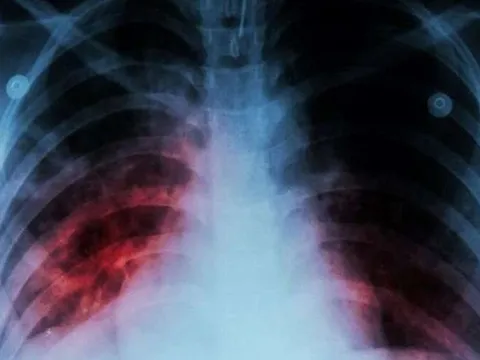

Căn bệnh truyền nhiễm nguy hiểm nhưng chưa được quan tâm đúng mức ở Việt Nam

Theo các chuyên gia, COVID-19 và lao đều là 2 căn bệnh truyền nhiễm nguy hiểm, lây lan qua không khí, ảnh hưởng đến sức khỏe con người nhưng bệnh lao vẫn chưa được quan tâm đúng mức.